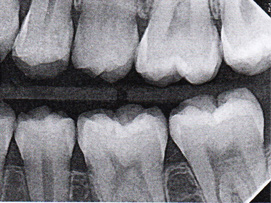

Interproximal insertion of SDF is demonstrated in different patients in Figure 3 through Figure 11. Various diameters and brands of soft dental picks may be used depending on the closeness of the proximal surfaces and ease of insertion; for example, some picks are designed for use in wider spaces between teeth. This protocol also offers versatility. Figure 3, for example, shows the simultaneous use of three thin soft dental picks to saturate proximal surfaces with SDF in a teenaged patient; the treated regions were subsequently covered with fluoride varnish (Figure 4). This patient was initially treated in April 2019 (Figure 5), with an identical re-application 3 months later. As shown in Figure 6, the December 2019 bitewing film revealed good results with the possible exception of the contact regions of the maxillary first and second molars. New SDF application was completed in the December appointment.

Fig 5. Three thin soft dental picks were used simultaneously for SDF proximal surface saturations in a teenaged patient (Fig 3). After 60 seconds, the treated regions were covered with 5% fluoride varnish (Fig 4). A comparison can be seen of pre-SDF-treatment bitewing films (Fig 5) and 8-month post-SDF bitewing films (Fig 6) for the patient shown in Fig 3 and Fig 4. Radiolucencies were similar or improved, except for contact of maxillary first and second molars.

Figure 5

Fig 6. Three thin soft dental picks were used simultaneously for SDF proximal surface saturations in a teenaged patient (Fig 3). After 60 seconds, the treated regions were covered with 5% fluoride varnish (Fig 4). A comparison can be seen of pre-SDF-treatment bitewing films (Fig 5) and 8-month post-SDF bitewing films (Fig 6) for the patient shown in Fig 3 and Fig 4. Radiolucencies were similar or improved, except for contact of maxillary first and second molars.

Figure 6